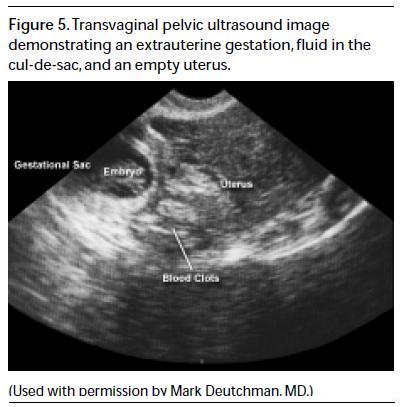

Ultrasound Findings Of Ectopic Pregnancy - Lieberman's ...

PELVIC: No active bleeding. Emergency Obstetrical Ultrasonography. Seminars in Roentgenelogy, Vol XXXIII, No 4(Oct), 1998: pp 339-343. Likelihood of Ectopic pregnancy based ultrasound, this is high-risk for ectopic pregnancy. ... Get Content Here

Point-of-Care First Trimester Pelvic Ultrasonography For The ...

EPIDEMIOLOGY OF ED PELVIC ULTRASOUND FINDINGS Emergency physician–performed point-of-care ultrasound will identify an intrauterine gestation in more than two thirds of symptomatic first trimester pregnancies. 4,13,14 Tayal et al4 documented intra- ... Fetch Content